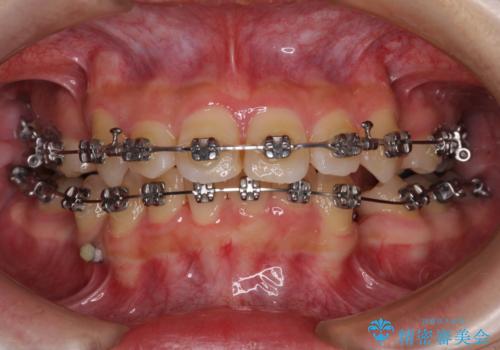

- 矯正装置

- メタルブラケット

- 上下の八重歯を気にして来院された患者様です。

非抜歯矯正で歯列を整えると、治療後に口元が今よりも突出する可能性が高かったため、上下左右の小臼歯4本を抜歯し、ワイヤー装置にて矯正治療を行うこととしました。

右上の八重歯の影響で、右側は上顎歯列が前方位の咬み合わせとなってしまっていたため、上顎は第一小臼歯を、下顎は第二小臼歯を抜歯することで咬み合わせや上下正中を調整することとしました。